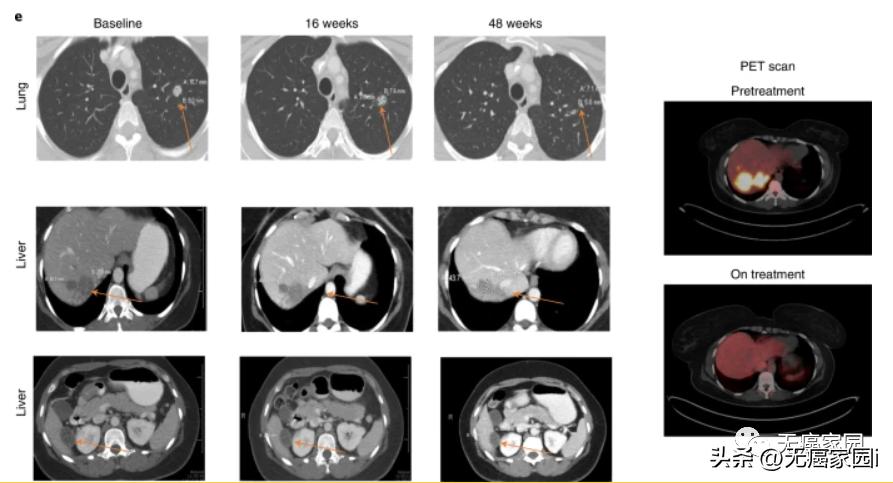

患者 G8 是一名 51岁的 MSS-CRC 患者,接受了21个月的化疗,在研究治疗开始前一线化疗取得进展,但在研究治疗期间继续伴随标准护理化疗并显示通过 ctDNA 和放射学评估接种疫苗后肿瘤消退的明确证据。计算机断层扫描显示, 16周内多处肺部病灶缩小,48周内多处肺部和一处肝脏病灶持续缩小 (图示)。